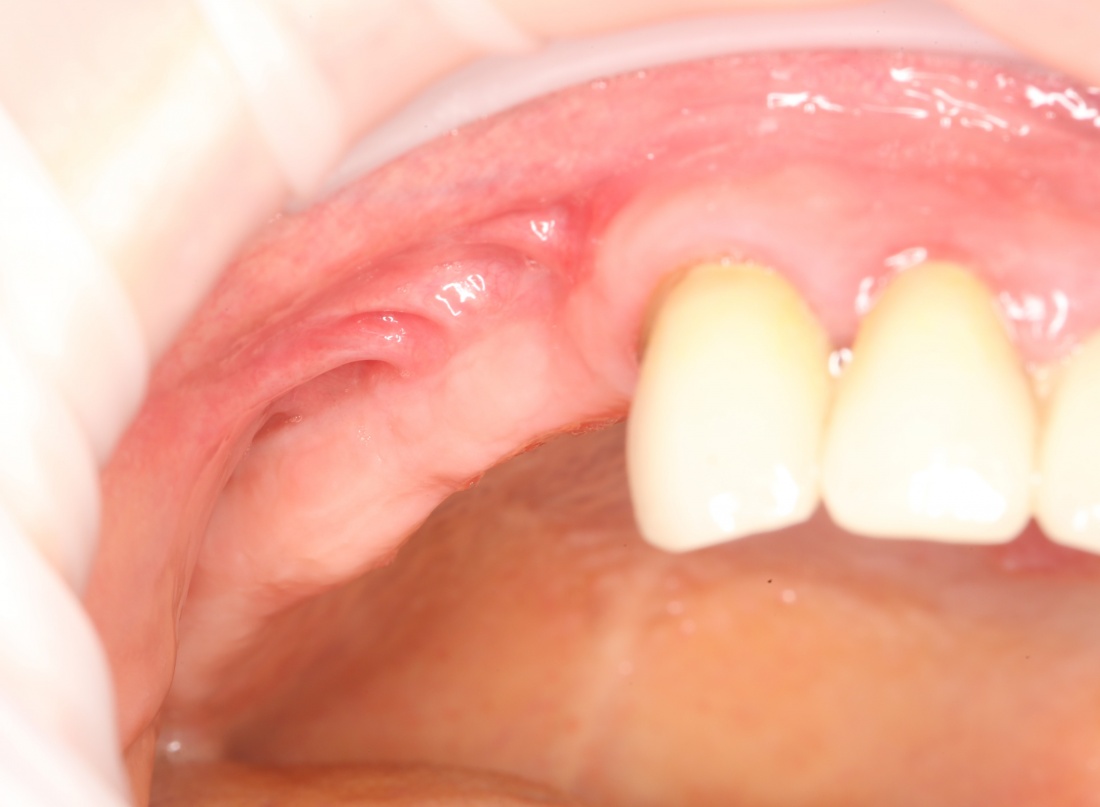

Если нет задачи ставить импланты — зачем открывать и скелетировать альвеолярный гребень? Чем больше операционная рана, тем больше потом будет проблем. Будьте рациональны:

Как видите, я перенес разрез вестибулярно, примерно в проекции предполагаемого субантрального доступа. Таким образом, я получаю тот же обзор при меньшей по площади ране. Это безопаснее. Такой доступ очень просто и легко зашивается, рана заживает быстрее и с минимальным дискомфортом. Кроме того, слизистая оболочка вершины альвеолярного гребня, где мы будем потом делать следующий разрез для установки имплантов, осталась неповрежденной, мы не оставили на ней рубцов, которые могут осложнить заживление при повторном входе для установки имплантов.